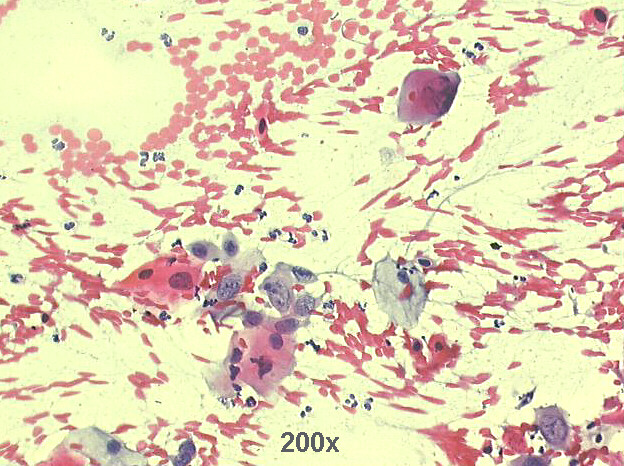

Cervico-vaginal cytology, 55-year old female,

4-year post radiation therapy for cervical squamous cell carcinoma

200x Pap staining